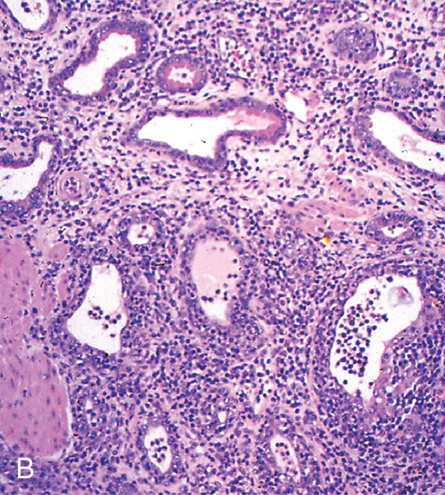

What is epididymitis?

inflammation of epididymis

Epididymitis

Inflammation of the epididymis

- Almost always affects the tail of the epididymis (different from spermatic granuloma of the epididymal head)

- Mostly ascending infection (accessory glands, urinary tract) → ecoli common

- Rarer haematogenous (e.g. Brucella spp) or trauma

What can occur secondary to epididymitis?

Secondary testicular degeneration/atrophy

By compression due to inflam or pyrexia